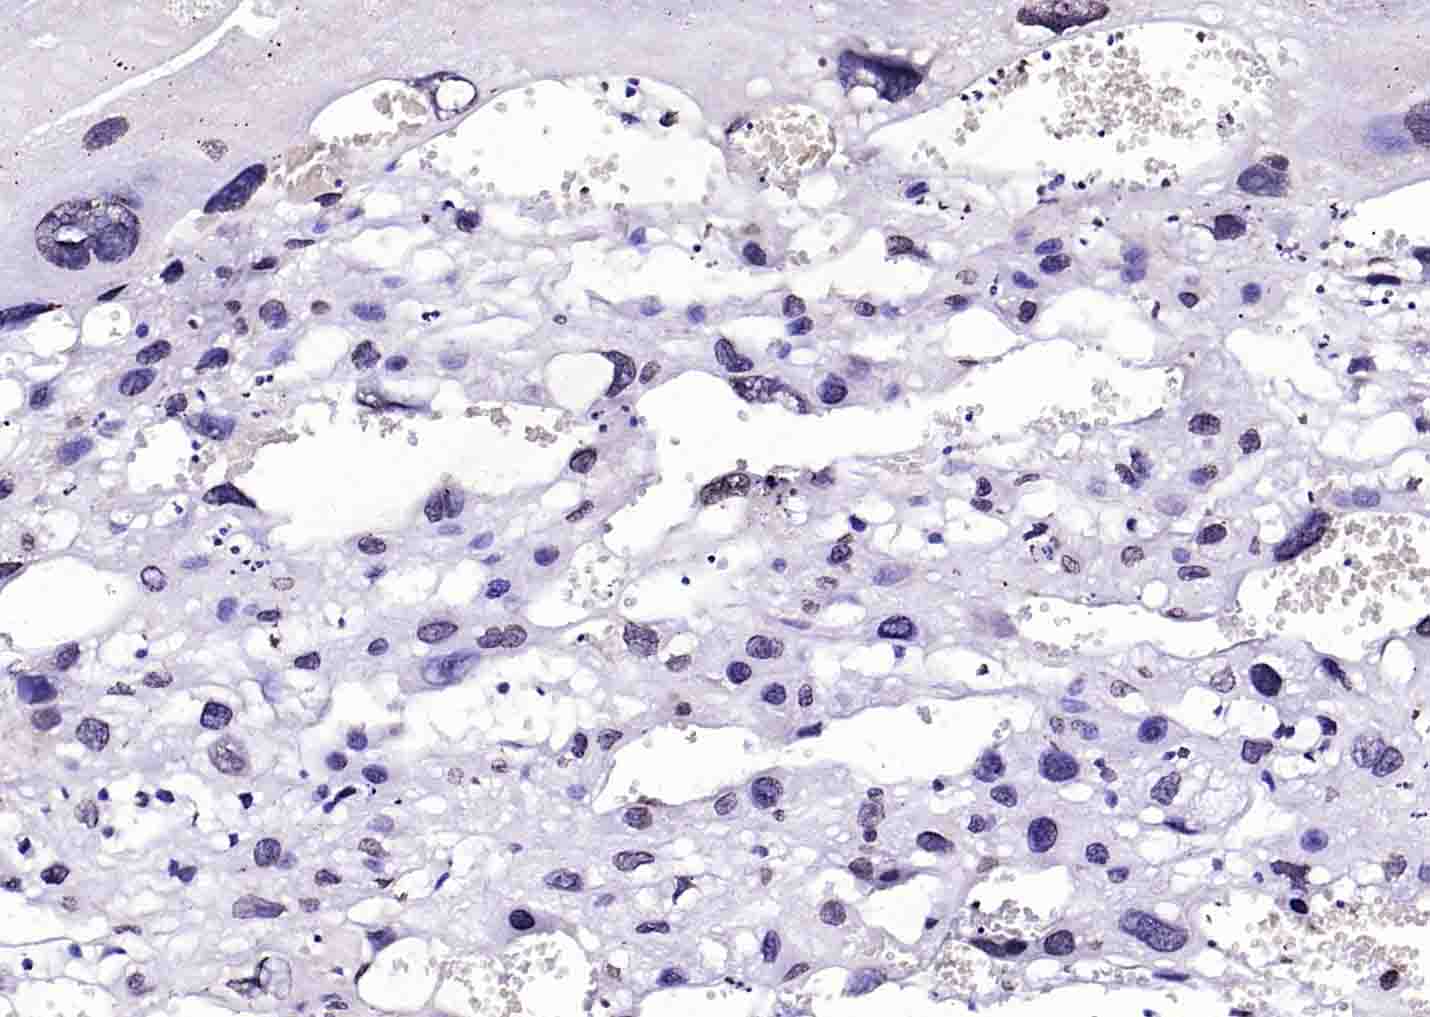

Antigen retrieval: citrate buffer ( 0.01M, pH 6.0 ), Boiling bathing for 15min; Block endogenous peroxidase by 3% Hydrogen peroxide for 30min; Blocking buffer (normal goat serum,C-0005) at 37℃ for 20 min;

Incubation: Anti-BRCA2/FANCB Polyclonal Antibody, Unconjugated(bs-1210R) 1:200, overnight at 4°C, followed by conjugation to the secondary antibody(SP-0023) and DAB(C-0010) staining